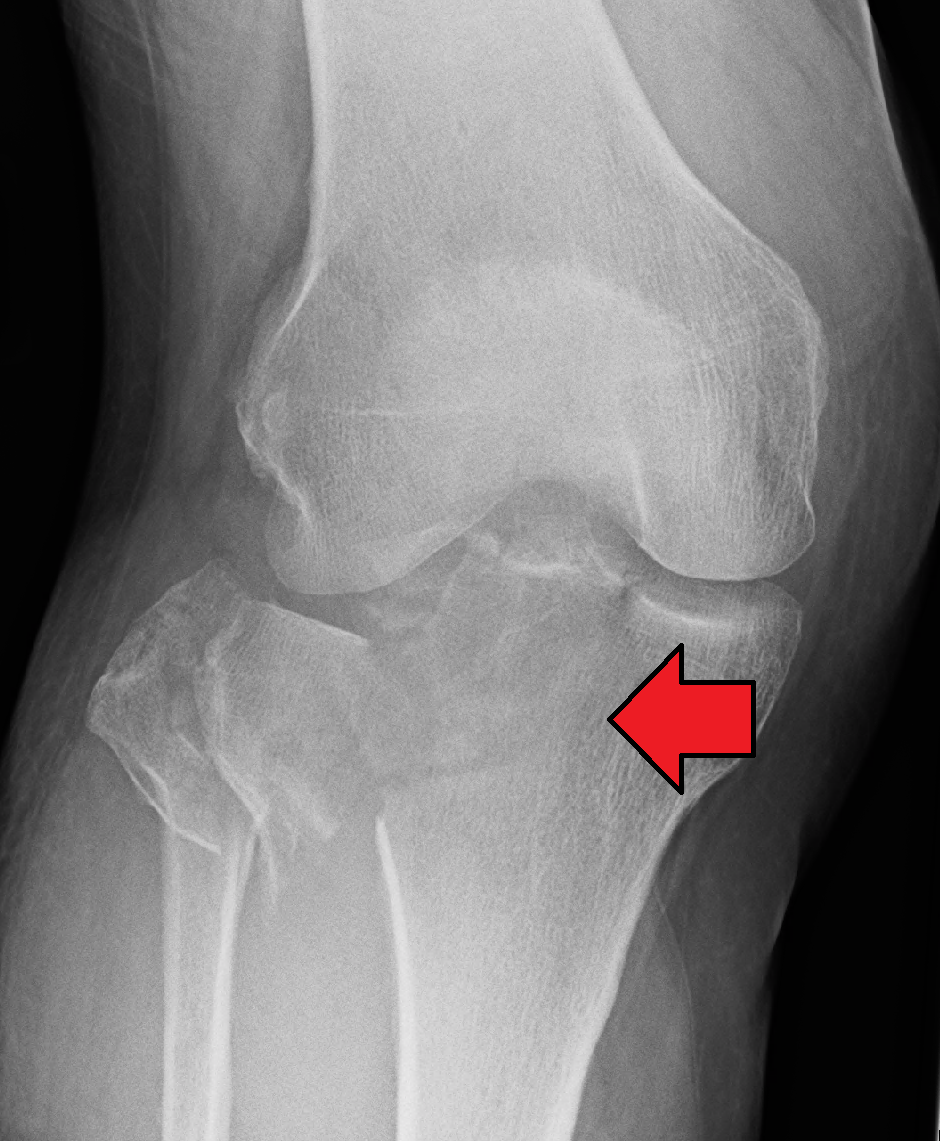

Clinical features of tibil fracture:

1) Pain, swelling and deformity are common. Deformity or angulation may be seen. The foot may be abnormally rotated.

2) Although vascular injuries are rare, it is important to assess distal pulses.

3) ‘Foot drop’ occurs with common peroneal nerve damage. Assess sensation in the first dorsal web space of the foot (deep peroneal nerve).

4) Ligamentous knee disruption is not uncommon and may be missed.